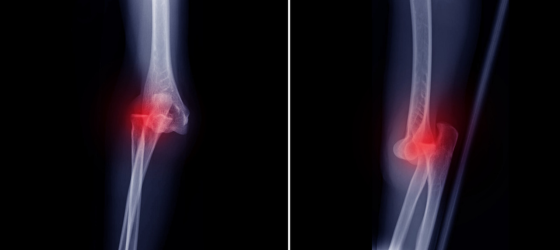

Al hablar de lesiones de rodilla, generalmente se enfoca en desgarros de menisco o ligamentos, que son típicos en deportes y la vida diaria. Pero la lesión más grave que esta articulación puede sufrir es una condición menos común, pero potencialmente devastadora: la luxación traumática de rodilla. Este diagnóstico debe ser aclarado, ya que esta es la percepción común del tema para sus víctimas. Una luxación traumática de rodilla no es una ‘articulación que se sale de lugar’. Es una herida de alta energía caracterizada por una separación completa del fémur (hueso del muslo) y la tibia (hueso de la espinilla) y la pérdida de varias estructuras importantes, incluidos ligamentos, vasos sanguíneos y nervios. Por supuesto, no debe confundirse con una luxación de rótula. En contraste, la luxación de rótula (donde un pequeño hueso frente a la rodilla se desplaza) es mucho más frecuente y mucho menos grave. Confundir las dos condiciones podría resultar en subestimar la gravedad y urgencia de una verdadera luxación de rodilla. Comprender esta diferencia es el primer paso para determinar los riesgos reales asociados con esta lesión.

Las implicaciones de una luxación traumática de rodilla no se limitan solo a la destrucción superficial de ligamentos; en lo que respecta a toda la pierna, puede amenazar su función normal. Existe un riesgo serio de complicaciones irreversibles por esta condición, ya que el tiempo es esencial para salvar una extremidad. Entre las complicaciones más graves se encuentran:

• Daño Vascular Crítico: La arteria poplítea — el principal vaso sanguíneo que suministra la parte inferior de la pierna — cruza justo detrás de la articulación de la rodilla. Esta arteria puede estirarse, desgarrarse o lesionarse durante una luxación, lo que ocurre en aproximadamente el 50% de los casos.